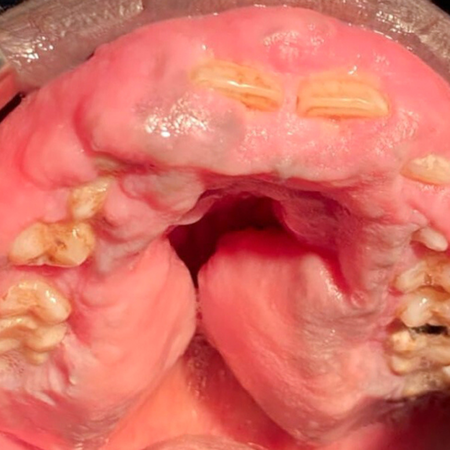

INTRODUÇÃO: A fibromatose gengival não sindrômica, também conhecida como fibromatose gengival idiopática, é uma condição rara, de etiologia desconhecida. As manifestações orais dessa condição são variadas e dependem da gravidade e da idade de acometimento. OBJETIVO: O objetivo deste artigo foi apresentar o manejo, sob anestesia geral, de um caso de fibromatose gengival difusa com acompanhamento clínico de três anos. MÉTODOS: É apresentado o relato do caso de um homem com 27...

INTRODUCTION: Non syndromic gingival fibromatosis also known as idiopathic gingival fibromatosis is a rare condition, with an unknown aetiology. The oral manifestations of this condition are varied and depend on the severity and age of involvement. OBJECTIVE: The aim of this paper was to present the management under general anesthesia of a diffuse gingival fibromatosis with a 3 years clinical follow-up. METHODS: We report a case of a 27-year-old sub-Saharian male who consulted the...